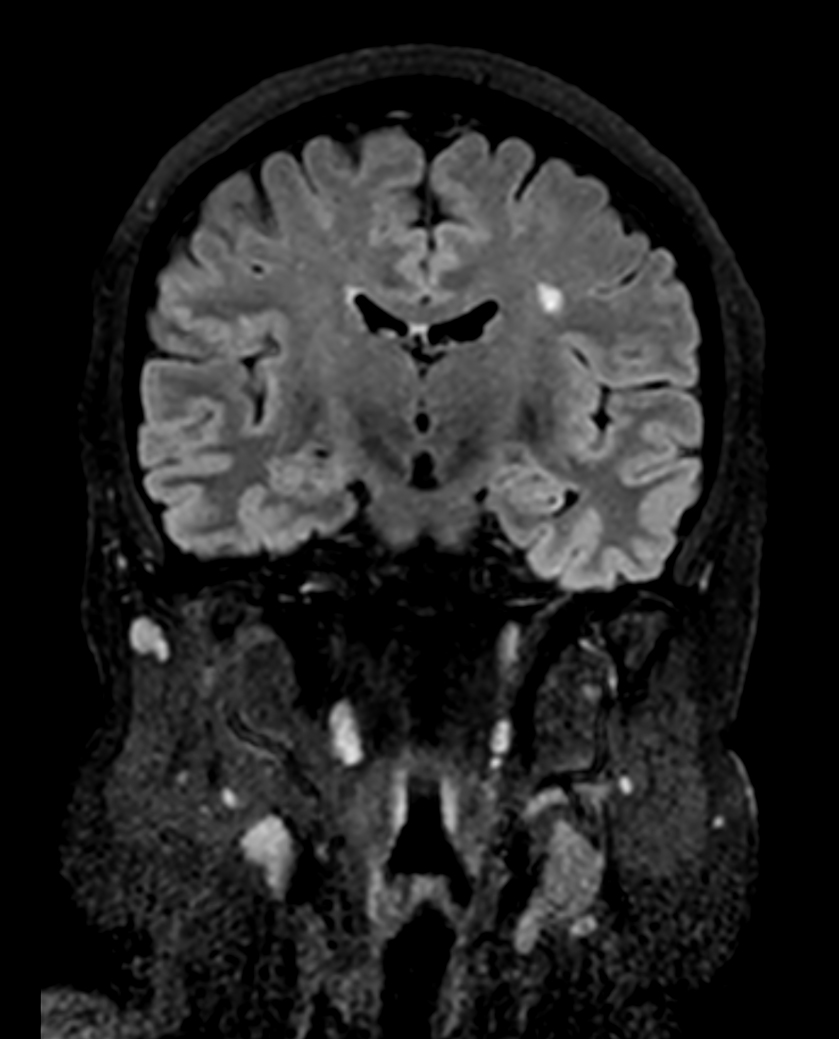

Coronal 3D BrainVIEW FLAIR (reformat)